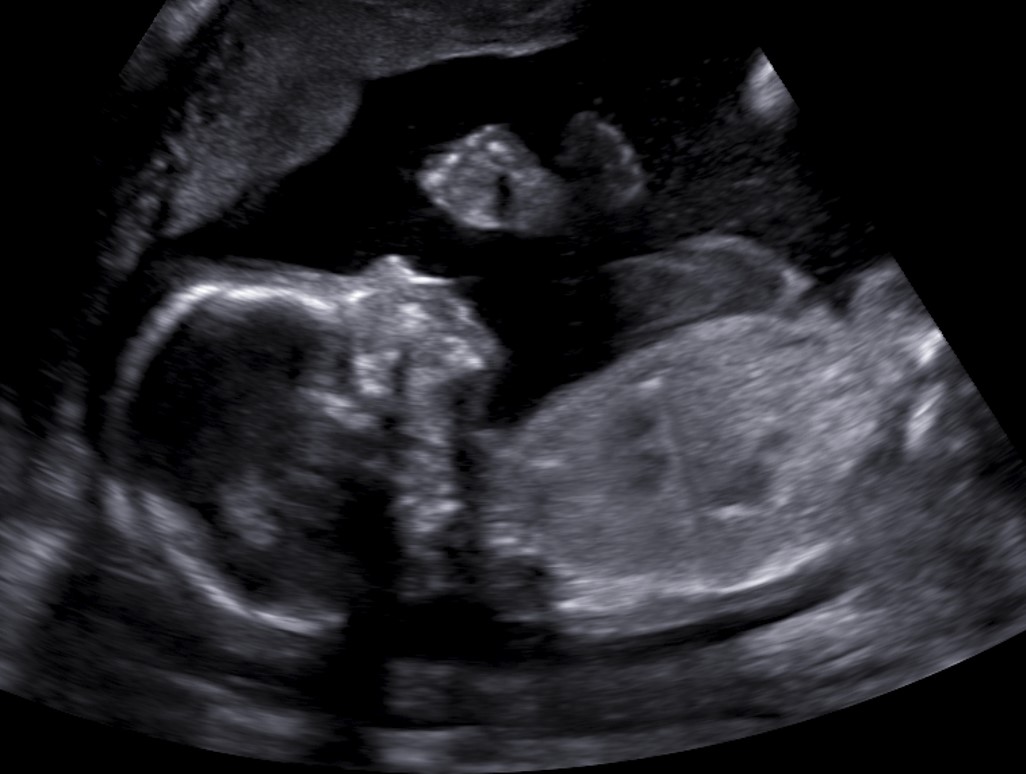

Den misstänka strukturella avvikelsen hos fostret kan i de fortsatta undersökningarna antingen bekräftas eller konstateras vara normal. Ibland behövs flera undersökningar för att utreda fyndet och det går inte alltid att fastställa en exakt diagnos under graviditeten.

Beroende på fynd går det utöver ultraljud att göra andra undersökningar, som magnetundersökning av fostret eller exaktare ultraljudsundersökning av hjärtat. Ibland kan fyndet sammanhänga med risk för kromosomrubbning eller en ärftlig sjukdom. Det går att undersöka fostrets kromosomer och gener genom provtagning av moderkakan eller fostervattnet.

På Enheten för forsterforskning kan man efter ultraljudet vid behov träffa en perinatolog och också en genetiker. Med dem kan man diskutera fyndet, vad det betyder och fortsatta undersökningsalternativ. Vid behov ges möjlighet att diskutera med en barnkirurg, barnneurolog eller annan specialläkare inom barnsjukdomar. Om rör sig om strukturella avvikelser i hjärtat utförs de vidare undersökningarna av en barnkardiolog.